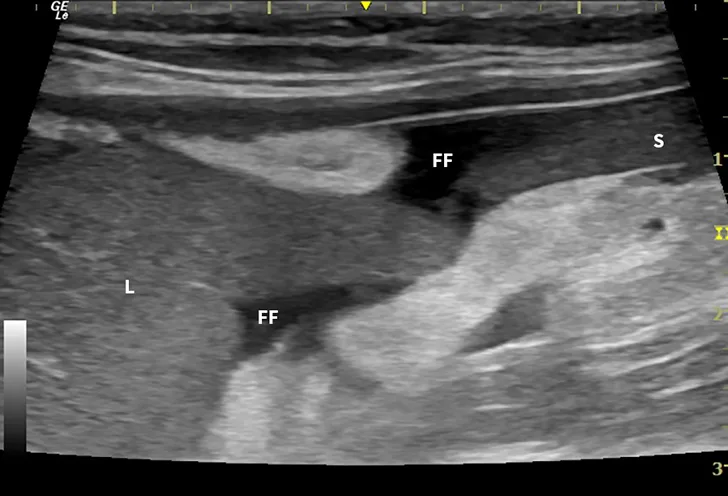

Dry FIP can manifest with organ dysfunction, uveitis, neurologic signs, fever, anemia, and/or lethargy and is caused by granulomas or immune complex deposition. Cats with wet FIP may have ascites or pleural effusion in addition to the aforementioned signs (Figure 1). Clinical presentation can vary from minor to life-threatening and involve almost any organ system.

Ultrasound image showing abdominal effusion in a cat with wet FIP. Anechoic fluid is present between organs, distending the abdomen. FF = free fluid; L = liver; S = spleen; K = kidney